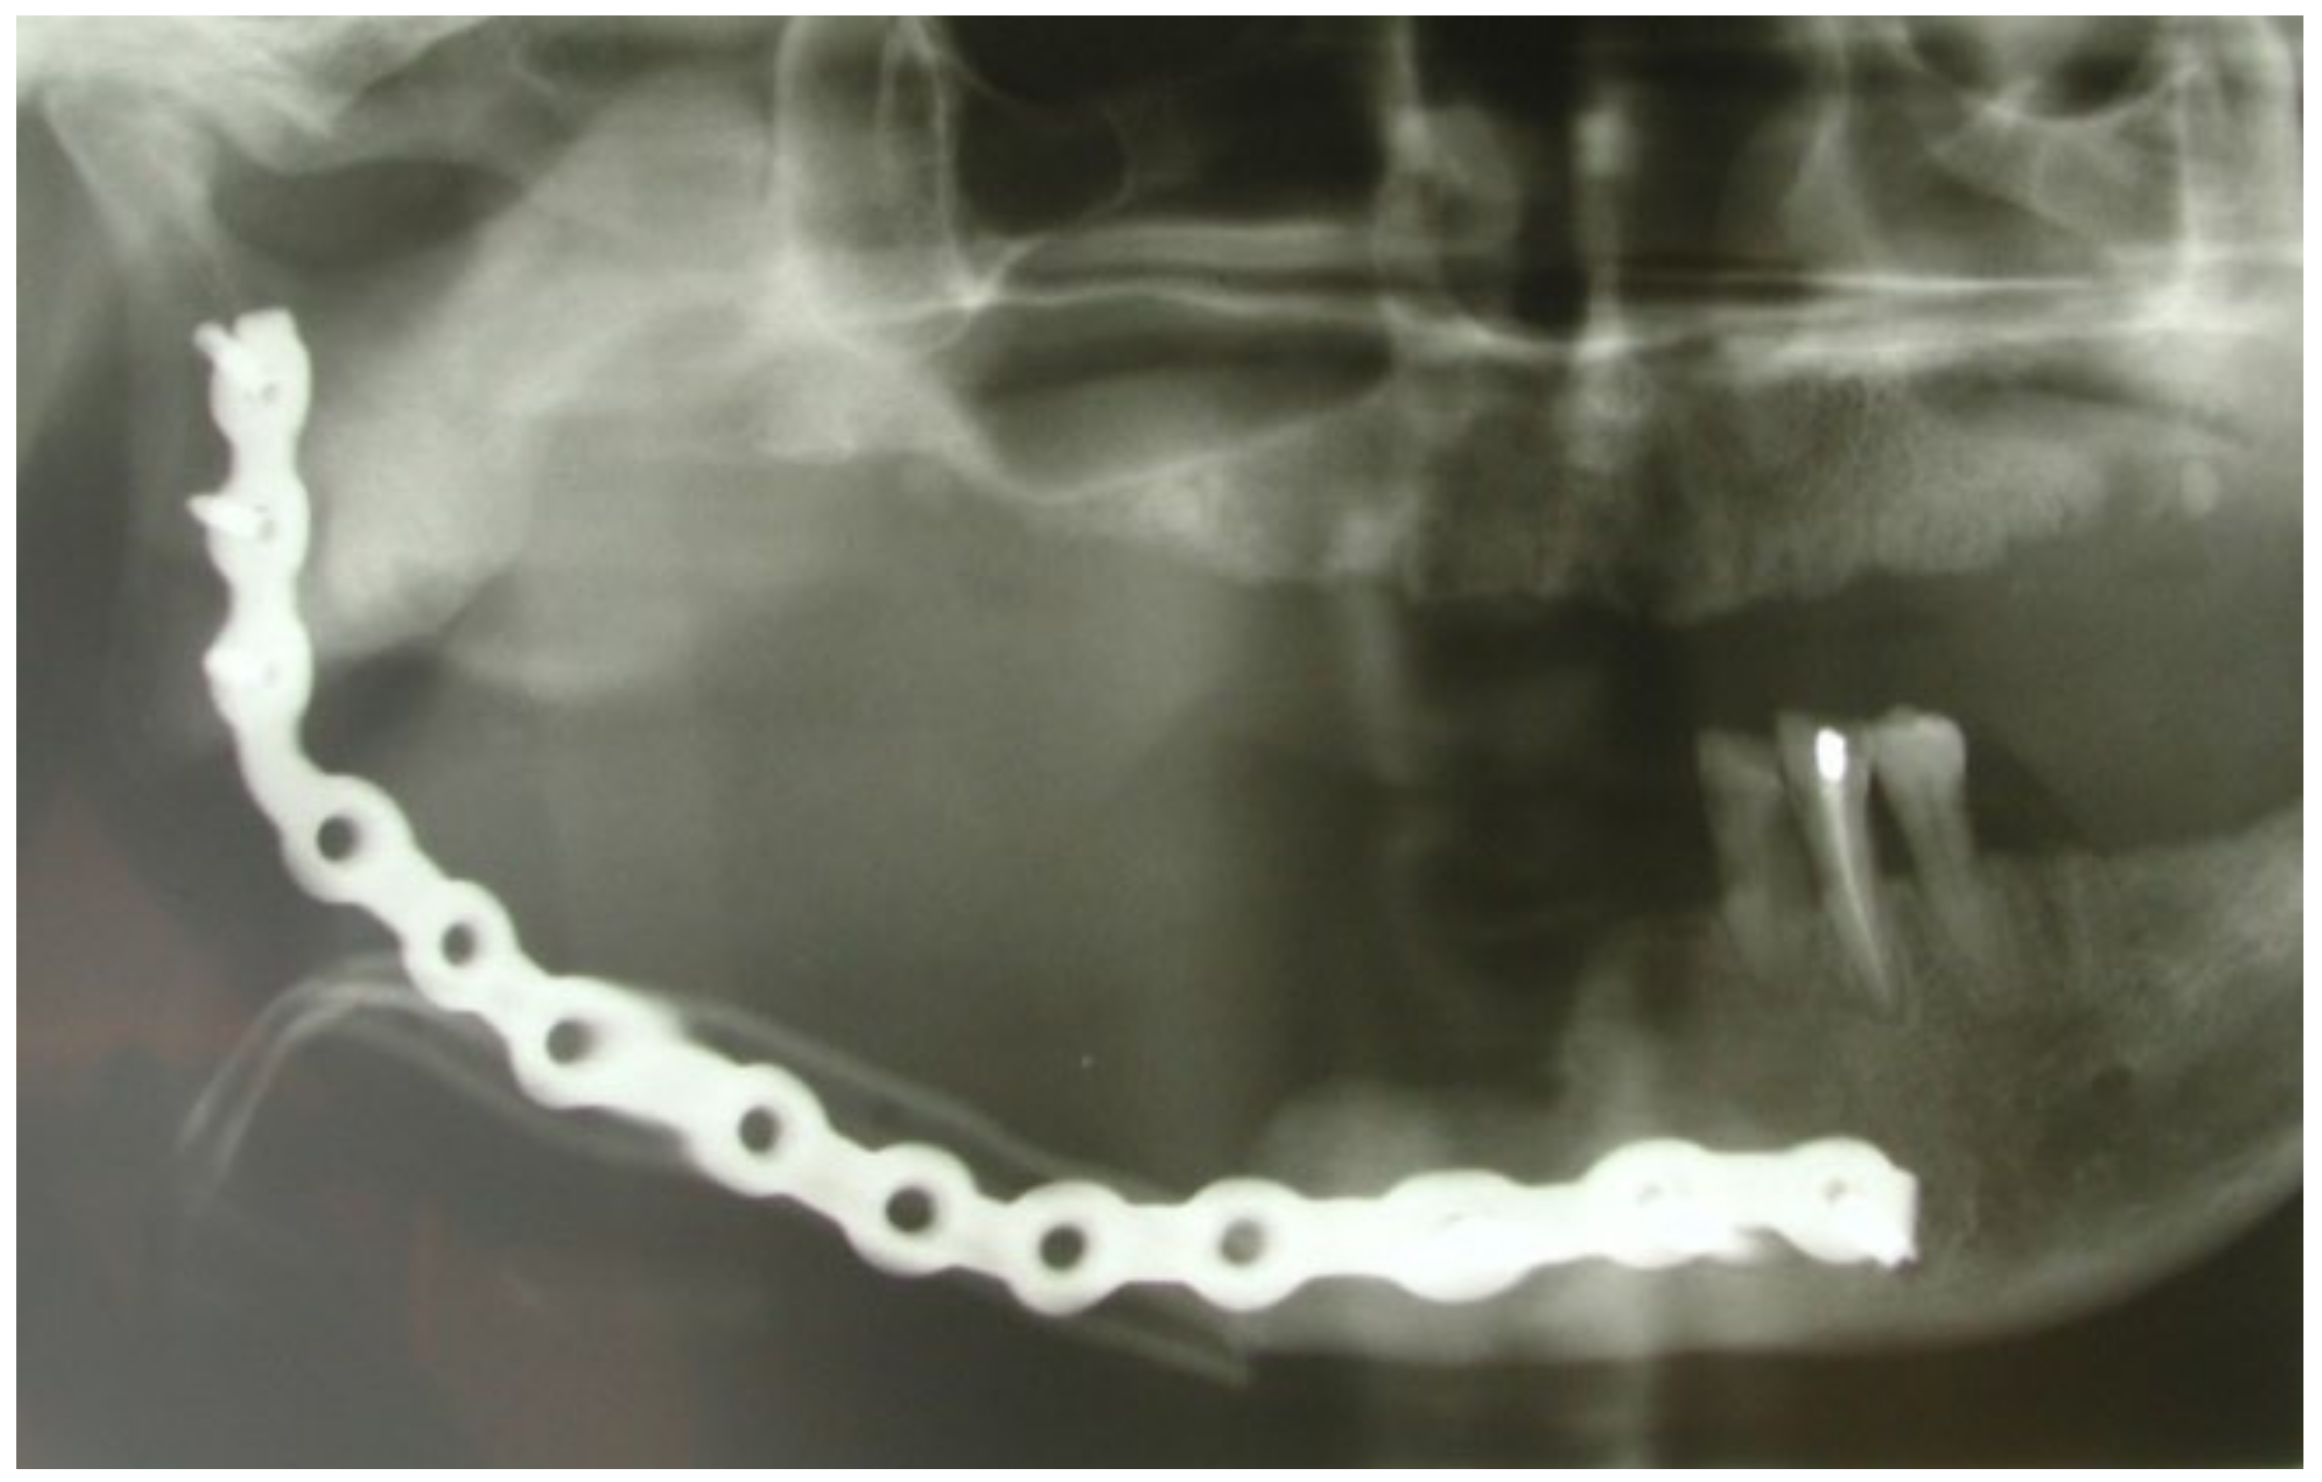

3.1. Clinical Case 1

3.2. Clinical Case 2

3.3. Clinical Case 3

3.4. Clinical Case 4

3.5. Clinical Case 5

3.6. Clinical Case 6